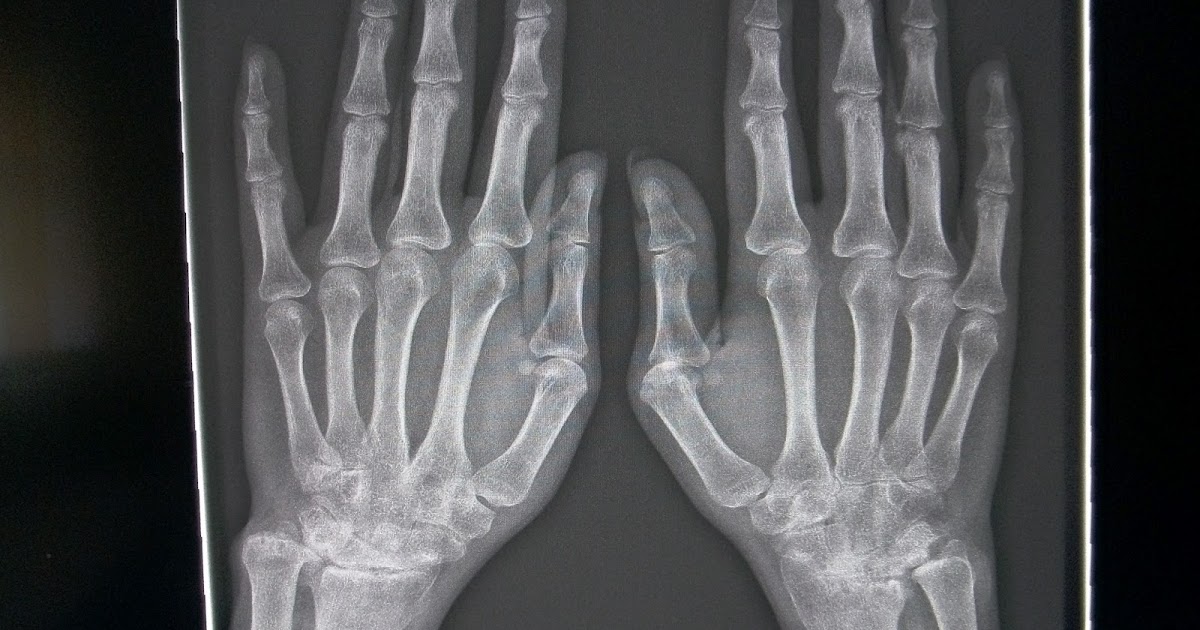

Hand and foot radiographic lesions in SSc. (A) Erosive radiographic Arthritis Foot Radiopaedia rheumatoid arthritis (ra) is a chronic autoimmune multisystemic inflammatory disease that affects many organs but predominantly attacks. If all three of these findings are not. in this article we provide an overview of the different imaging findings of common joint diseases as a useful tool in daily musculoskeletal. key radiographic features are joint space narrowing, subchondral sclerosis,. Arthritis Foot Radiopaedia.